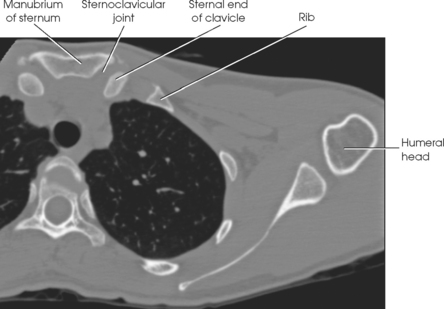

The acromioclavicular (AC) articulation between the acromion process of the scapula and the acromial extremity of the clavicle forms a synovial gliding joint (see Fig. 5-12). It permits gliding and rotary (elevation, depression, protraction, and retraction) movement. Because the end of the clavicle rides higher than the adjacent surface of the acromion, the slope of the surfaces tends to favor displacement of the acromion downward and under the clavicle.

The sternoclavicular (SC) articulation is formed by the sternal extremity of the clavicle with two bones: the manubrium and the first rib cartilage (see Fig. 5-12). The union of the clavicle with the manubrium of the sternum is the only bony union between the upper limb and trunk. This articulation is a synovial double-gliding joint. The joint is adapted by a fibrocartilaginous disk, however, to provide movements similar to a ball-and-socket joint: circumduction, elevation, depression, and forward and backward movements. The clavicle carries the scapula with it through any movement.